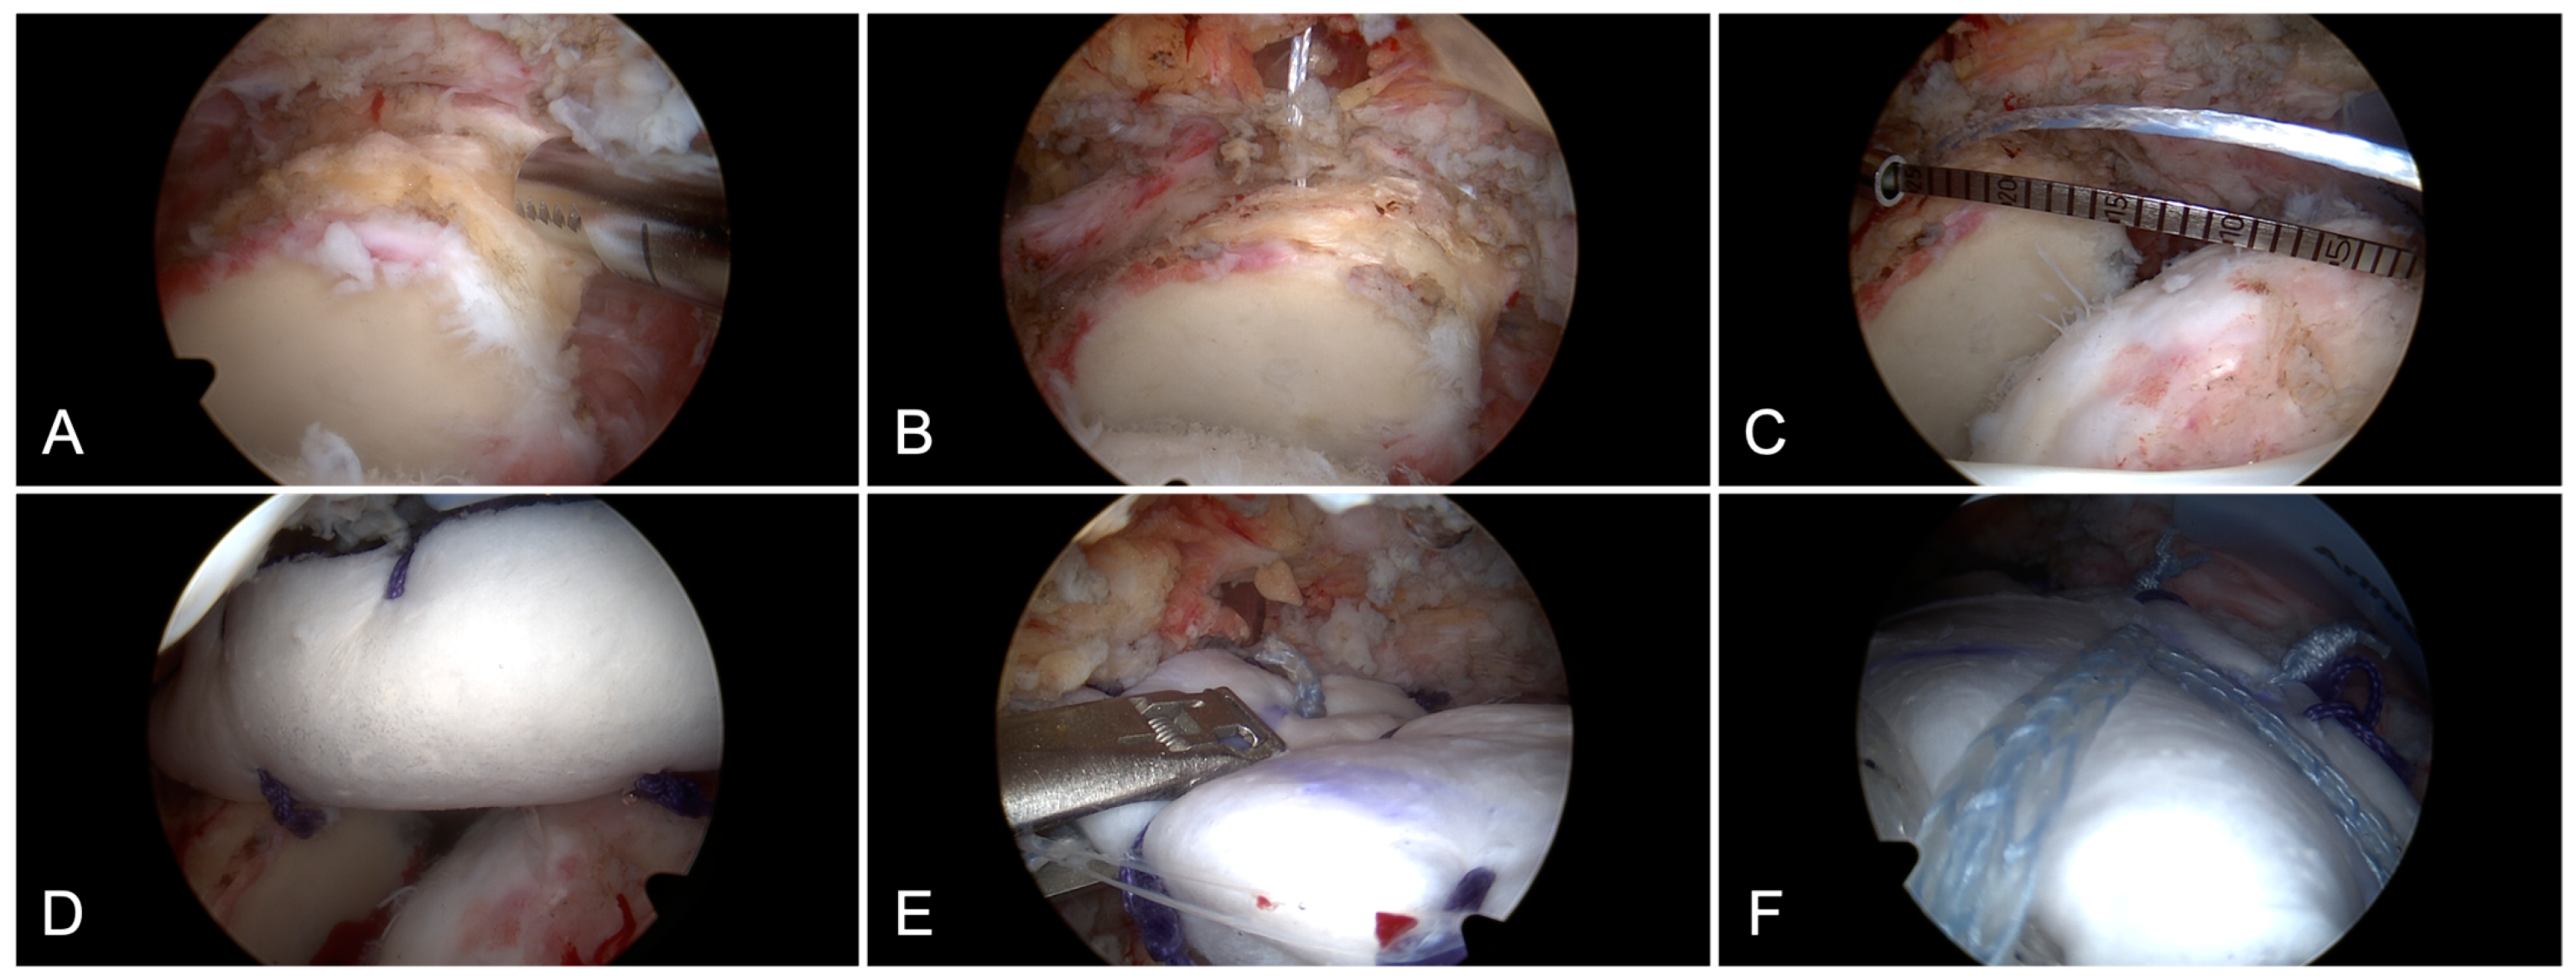

2.1. Surgical Technique

- Muench, L.N.; Pogorzelski, J.; Scheiderer, B. Arthroskopische Superiore Kapselrekonstruktion Mit Einem 6 Mm Dicken Azellulären Dermalen Allograft Bei Irreparablen Posterosuperioren Rotatorenmanschettenrupturen. Oper. Orthopädie Traumatol. 2022, 34, 13–20. [Google Scholar] [CrossRef] [PubMed]